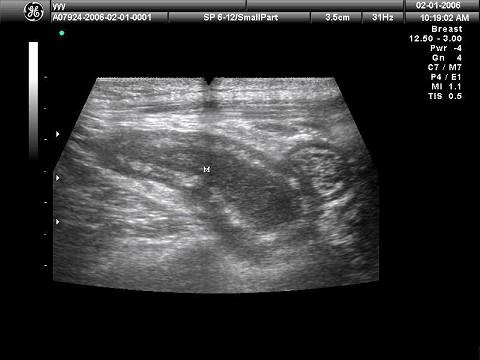

问题 患者,女性,转移性右下腹疼痛4小时,超声见一长条低回光团,边界不清,如图所示,考虑为?(?)

选项 A.肝管结石 B.胆囊炎 C.附件炎 D.阑尾炎 E.肠梗阻

答案 D